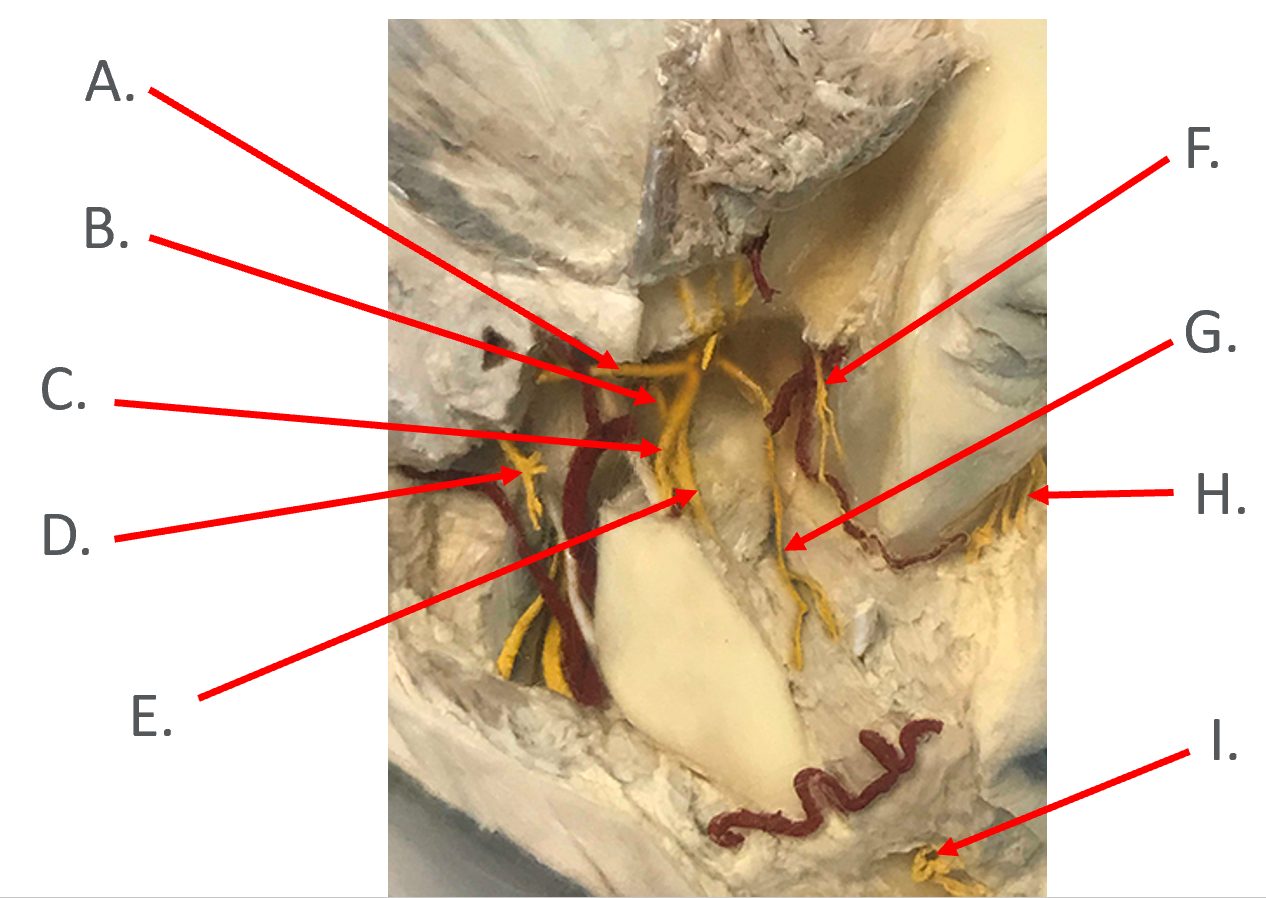

A.

B. Chorda Tympani (branch of CN 7)

C. Inferior Alveolar n. (branch of CN 5.3)

D. Facial n. (CN 7)

E. Lingual n. (branch of CN 5.3)

F. Posterior Superior Alveolar n. (branch of CN 5.2)

G.

H.

I. Mental n.

H. Infraorbital n. (branch of CN 5.2)

I. Mental n. (branch of CN 5.3)